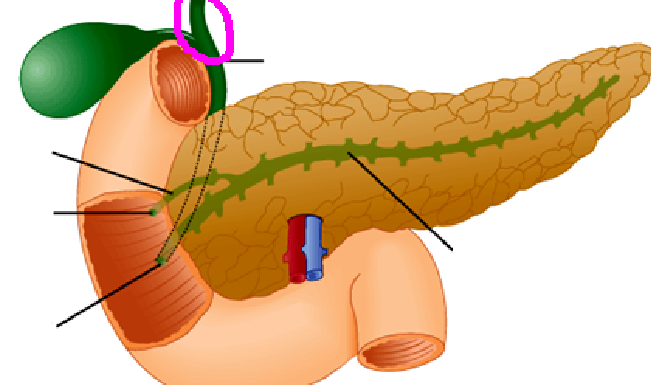

Fundus of gallbladder

orange highlight

Body of gallbladder

green highlight

Neck of gallbladder

yellow highlight

Cystic duct

pink highlight

Left hepatic ducts

Right hepatic ducts

Common hepatic duct

Common bile duct

Duodenal papilla within duodenum